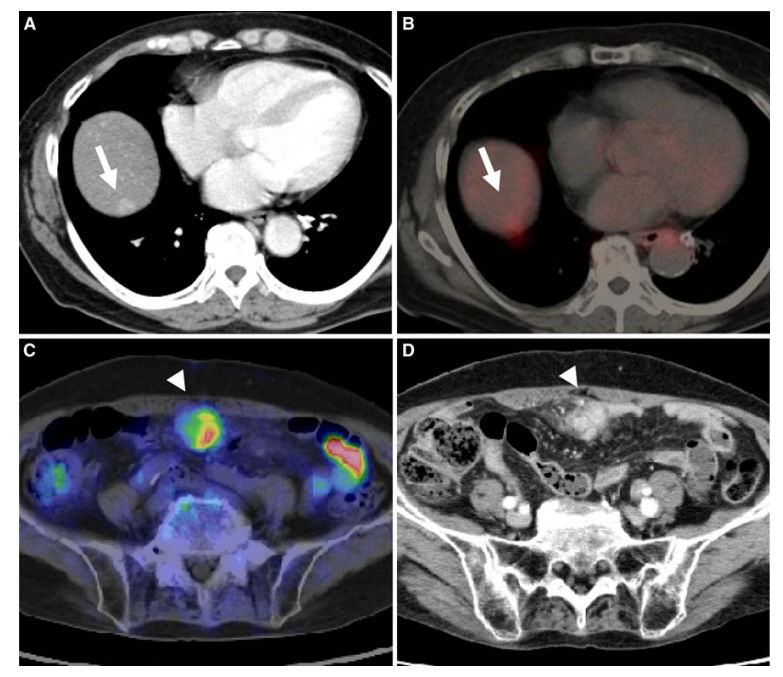

①对肿瘤进行分期,通过1次检查能够全面评价有无淋巴结转移及远处器官的转移(证据等级 1,推荐 A);

②再分期,因PET/CT功能影像不受解剖结构的影响,可以准确显示解剖结构发生变化后或者解剖结构复杂部位的复发转移灶(证据等级 2,推荐 B);